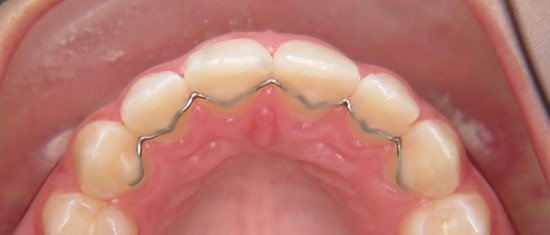

Gesunde und schöne Zähne zaubern euch nach dem Entfernen der festen Zahnspange ein strahlendes Lächeln ins Gesicht! Damit das ein Leben lang so bleibt, stabilisieren wir das tolle Ergebnis mit herausnehmbaren oder noch lieber mit festen Zahnspangen, den so genannten Retainern (von engl. to retain = zurückhalten). Herausnehmbare Retainer können aussehen wie übliche Kinderzahnspangen oder wie transparente Aligner. Ein festsitzender Retainer ist ein unauffälliger, dünner Draht, der im Ober- und Unterkiefer auf die Innenseite der sechs Frontzähne geklebt wird.

Fester Retainer auf der Innenseite der oberen Frontzähne

In unserer kieferorthopädischen Praxis in Mannheim empfehlen wir vor allem feste Retainer, da der Draht die Zahnstellung zuverlässig und langfristig erhält, ohne dass er stört. Feste Retainer sind leicht zu reinigen ist und außerdem auf Dauer eine kostengünstige Lösung. Als erfahrene Kieferorthopäden wissen wir, dass unsere Patienten mit festsitzenden Retainern einfach am besten zu recht kommen.